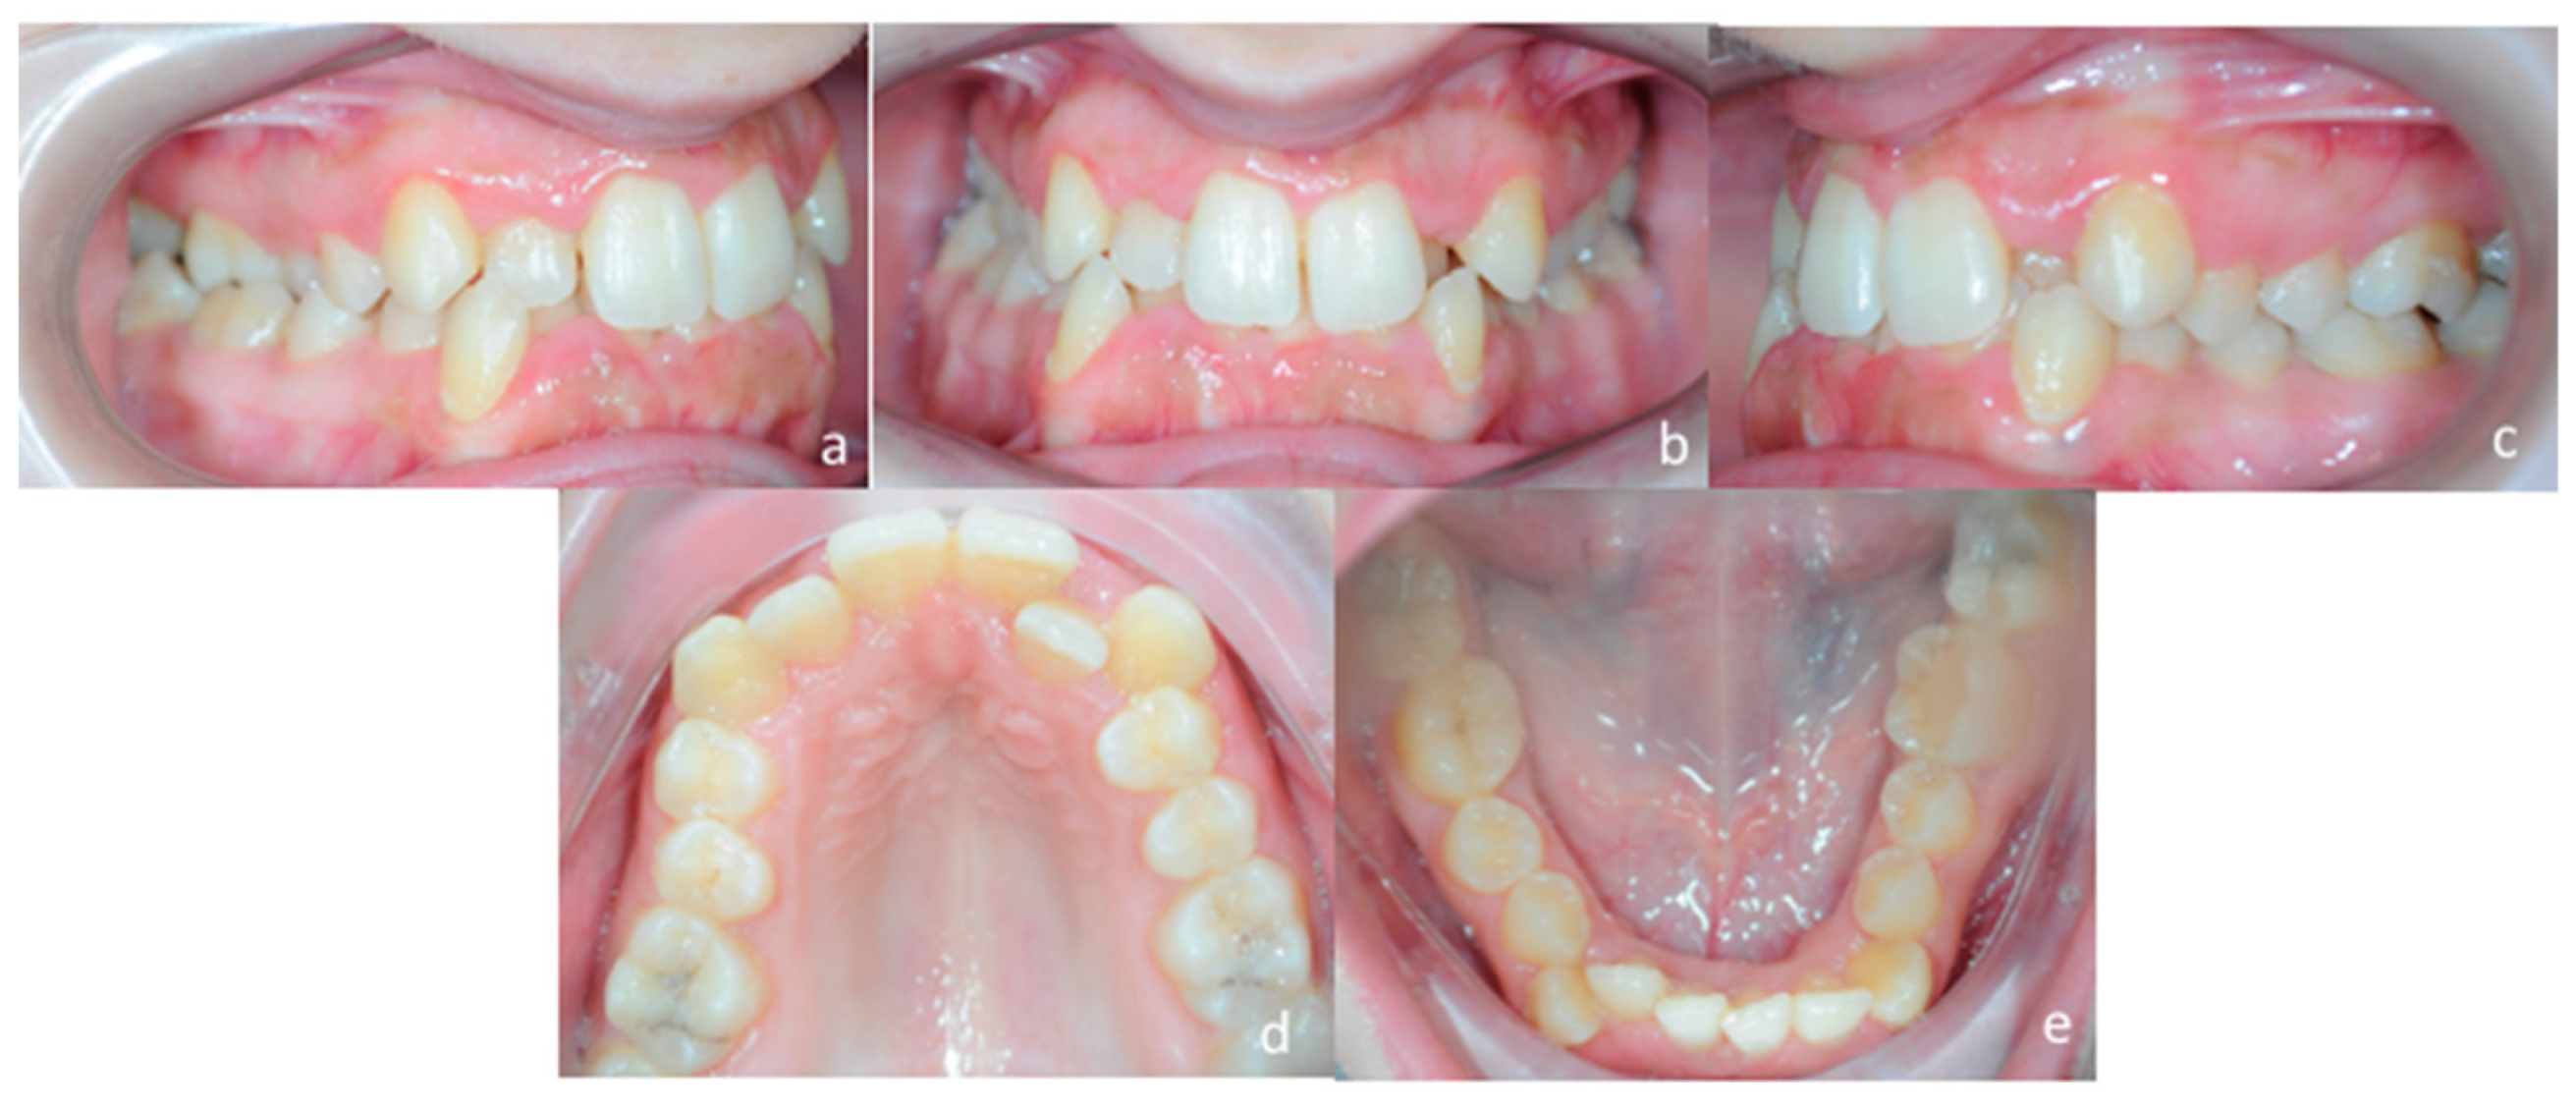

A 25 years old female attended consultation for orthodontic treatment to enhance the aesthetic of the smile. In particular, the chief complain was the crowded teeth along with the presence of wide buccal corridors while smiling. Facial analysis revealed retrognatic profile with labial competence, no gingival exposure during smiling along with extensive buccal corridors (Figure 7a–c). Intra-oral examination revealed class I molar and canine relationships, significant maxillary and mandibular crowding, mild maxillary transversal deficiency with cross-bite on the right side due to mandibular shift toward cross-bite side, significant anterior overbite (Figure 8a–e). Panoramic examination showed healthy condition of the upper first molars that would support the dental anchorage of the MSE device (Figure 9). Cephalometric analysis (Figure 10a,b) confirmed that the patient presented skeletal class I maxillo-mandibular relationship with retruded profile, mesiofacial growth pattern and anterior overbite. Patient approved the usage of photographic and radiographic records for the purpose of publication, by signing a specific form.

Figure 8.

Intra-oral patient’s examination. (a) Right lateral occlusion, (b) front view, (c) left lateral occlusion, (d) occlusal view of the maxillary arch, (e) occlusal view of the mandibular arch.